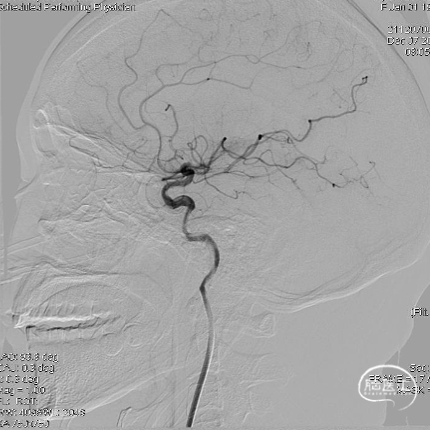

术前造影:提示左侧颈内动脉起始段闭塞,左侧大脑后动脉后交通开放,代偿左侧大脑中动脉部分供血区。

造影证实开通,远端未见闭塞。

术后造影:

术后造影及CT提示:左侧颈内动脉开通,血流灌注达mTICI 2c级,造影剂无外渗,远端分支血管部分闭塞。